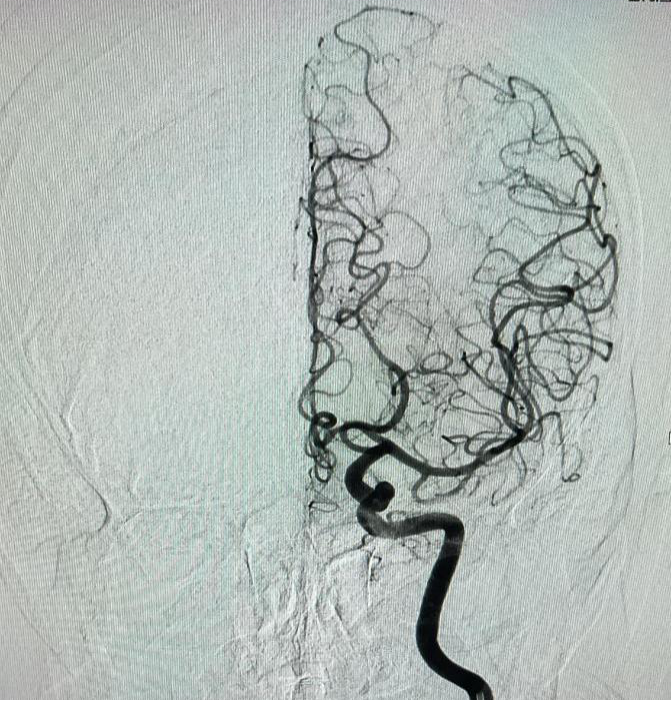

颅脑血管造影

数字减影血管造影的原理是将注入造影剂前后拍摄的两帧X线图像经数字化输入图像计算机,通过减影、增强和再成像过程来获得清晰的纯血管影像,同时实时地显现血管影。